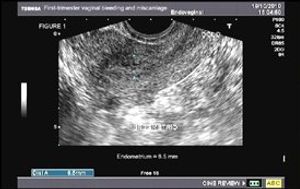

Sagittal image from a transvaginal sonogram in a patient with bleeding after a spontaneous abortion. The endometrium (between cursors) was thick and heterogeneous, measuring 8.5 mm in thickness (Fig1). Color doppler image in same patient shows focal flow (Fig. 2 - arrow) within the heterogeneous endometrium.